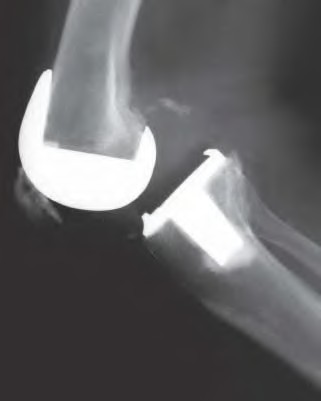

A 60-year-old male tennis player undergoes a unicompartmental knee arthroplasty (UKA) shown in Figures A and B. Which of the following statements regarding this procedure is true?

Figures A and B depict radiographs of a unicompartmental knee arthroplasty (UKA). UKA kinematics have been shown to most closely approximate native knee kinematics.

In an in vitro cadaver study, Patil et al found that TKA significantly changed knee kinematics while the unicompartmental replacement preserved normal knee kinematics.

Fisher et al performed a retrospective study comparing the short-term outcomes of small-incision unicompartmental knee arthroplasty (UKA) with standard total knee arthroplasty (TKA) in 91 consecutive patients older than 70 years. They found: 1) Blood loss was significantly more for the TKA group, as was the need for blood transfusion. 2) Patients with unicompartmental replacements had a much quicker return of function and discontinuation of pain medication. 3) While knee scores and ROM were similar preoperatively, both were better in the unicompartmental group at each postoperative time interval. 4) Narcotic use and length of hospital stay were also significantly less for the unicompartmental group. Therefore answers 2,3,4 and 5 are false.